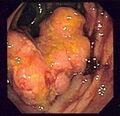

Endoscopic image of colon cancer identified in sigmoid colon on screening colonoscopy in the setting of Crohn's disease

Appearance of the inside of the colon showing one invasive colorectal carcinoma (the crater-like, reddish, irregularly shaped tumor)